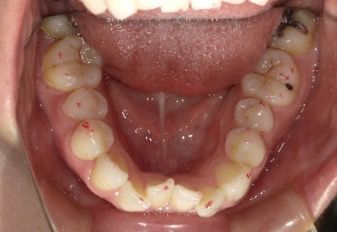

30代 女性 叢生

BEFORE

30代 女性 叢生 BEFORE

• 上下に叢生が見られる。歯列の拡大、臼歯の遠心移動、IPRを組み合わせてインビザラインで治療を行う事にした。

• 下顎前歯が1本欠損しているので、上顎の正中と下顎の正中はずれてしまう。

• コンプライアンスが良く、治療に協力的だったため治療はスムーズに進んだ。

30代 女性 叢生 術前上

30代 女性 叢生 術前下